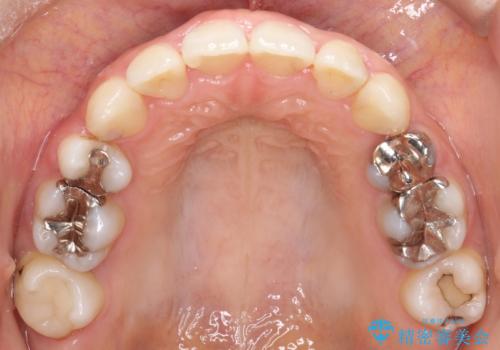

- 上下の歯の中心(正中)のズレと、口元の見た目を気にされて来院されました。精密な検査の結果、咬み合わせのバランスを整えながら、正中線を一致させる治療が必要と判断。患者様のご希望に合わせ、透明で目立ちにくいインビザライン(マウスピース矯正)による治療計画を立案しました。歯列全体を奥(遠心)へ移動させるためにゴムかけを併用。さらに、見た目を改善するため、既存の金属の被せ物をセラミッククラウンに交換することも治療計画に組み込みました。

今回の矯正治療では、透明なマウスピース型の装置インビザラインを使用しました。歯列を奥へ動かす遠心移動の効率を高めるため、患者様ご自身にゴムかけも行っていただきました。この併用によって、歯をより正確かつスムーズに動かすことができ、上下の歯の中心である正中線を一致させることが可能になりました。また、治療の最終段階では、以前から入っていた金属の被せ物を、天然歯に近い色合いのセラミッククラウンに交換。矯正治療と審美治療を組み合わせることで、機能的な咬み合わせの改善に加え、金属が見えない、より自然で美しい口元を獲得していただけました。